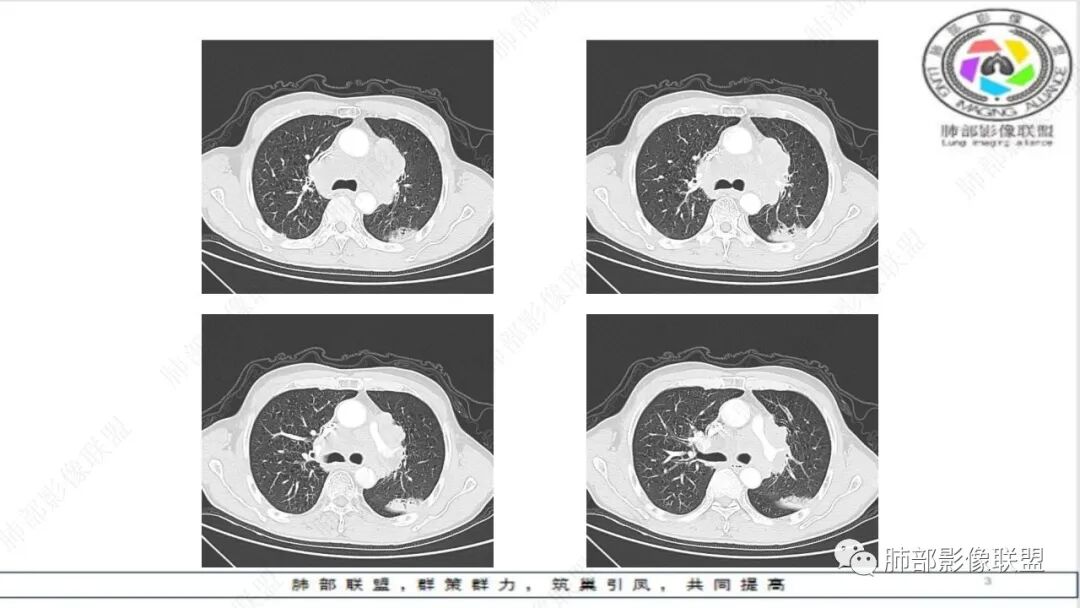

纵隔内及左肺门淋巴结肿大,冰冻纵膈,肺动脉包绕受压,支气管受压变窄,呈针孔样。双肺上叶结节及条索考虑陈旧结核。老年男性,慢支肺气肿背景,考虑小细胞肺癌。左肺上叶后段大片实变,不符合小细胞肺癌原发灶,二元论感染灶?肺栓塞?

晨读:男,65,咳喘1月余,加重3天。胸部CT:纵隔、肺门多发淋巴结肿大融合,冰冻纵隔,冰冻肺门,大血管包埋挤压,左肺A主干变窄。平扫密度较均匀,不均匀强化,灶性低密度。右上肺多发实性结节,中轴间质分布;左上叶针孔状支气管,后段胸膜下近楔形斑片影,融冰?考虑Ca,SCLC,并左上叶PTE?鉴别淋巴瘤。

晨读,老年男性,肺气肿背景,左肺门及纵隔内多发肿大淋巴结,部分融合、包埋血管,冰冻状,左肺上叶支气管受压变窄。双肺散在小结节,左肺上叶胸膜下楔形实变。考虑恶性病变,小细胞肺癌,鉴别淋巴瘤、转移瘤

老年慢性,肺气肿背景,纵隔左肺门明显多发肿大淋巴结且融合,密度相对均匀,增强后轻中度强化,偏纵隔右侧淋巴结坏死明显,左肺支气管可见受压变窄,呈针孔样改变。左肺上叶叶间裂上方山丘状混合磨玻璃病灶,内密度不均可见空泡。考虑小细胞肺癌(娘小崽大)。

联盟晨读病例:左肺门软组织肿块,纵隔淋巴结肿大相互融合,左肺上叶支气管狭窄,血管受压,左肺上叶阻塞性肺炎,考虑左肺上叶中心型肺癌伴纵隔淋巴结肿大,左肺上叶阻塞性肺炎。小细胞癌。

阻塞性肺炎不重

小细胞肺癌的支气管内肿瘤多来自淋巴结转移,小细胞肺癌侵入支气管是以组织间隙侵袭生长为主,对应的是鳞癌的气管内生长,明显的阻塞性肺炎